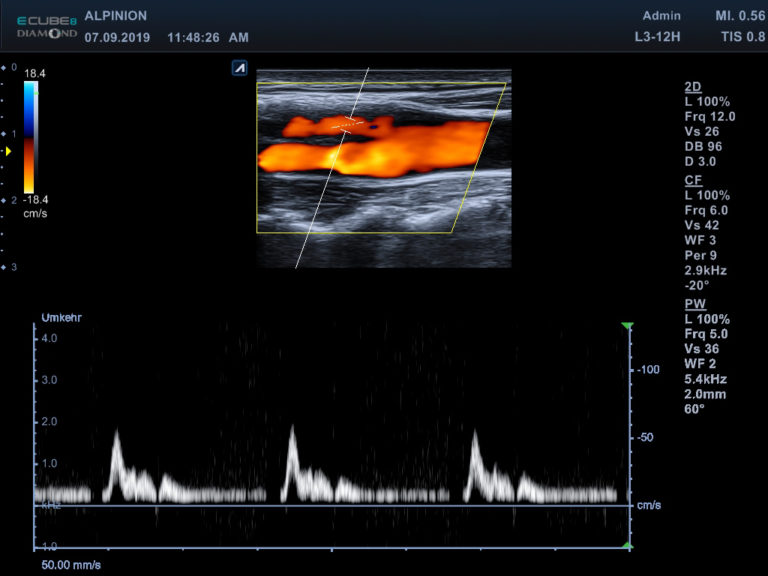

Ultrasonograf Alpinion E-CUBE 8 to jeden z najczęściej wybieranych systemów do badań naczyniowych.

Potwierdziło to już bardzo wielu lekarzy, potwierdzają to także obrazy kliniczne uzyskane przez naszych inżynierów.

Wybrane obrazy kliniczne